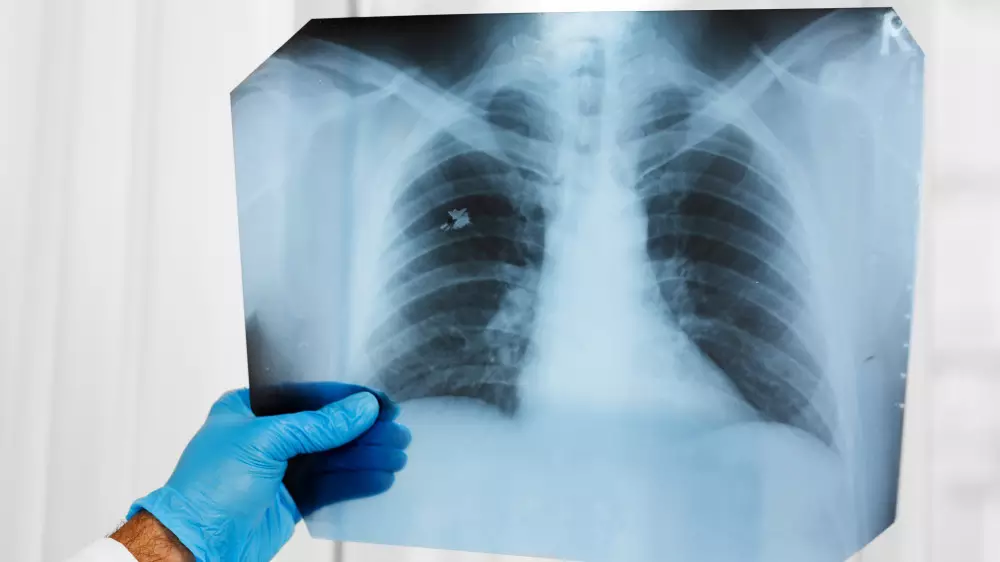

Для определения расы нейросети нужны рентген-снимки и компьютерная томография грудной клетки, кистей рук, шейного отдела позвоночника и маммография для анализа представителей женского пола. Указывается, что она, в частности, обращает внимание на физические характеристики и общее состояние здоровья, которое, по статистике, у чернокожих хуже.

Доказательства того, что алгоритм может считывать расу с медицинских снимков человека, появились из тестов на пяти типах изображений, используемых в радиологических исследованиях. На снимках были изображены пациенты, которые идентифицировали себя как чернокожих, белых и азиатов.